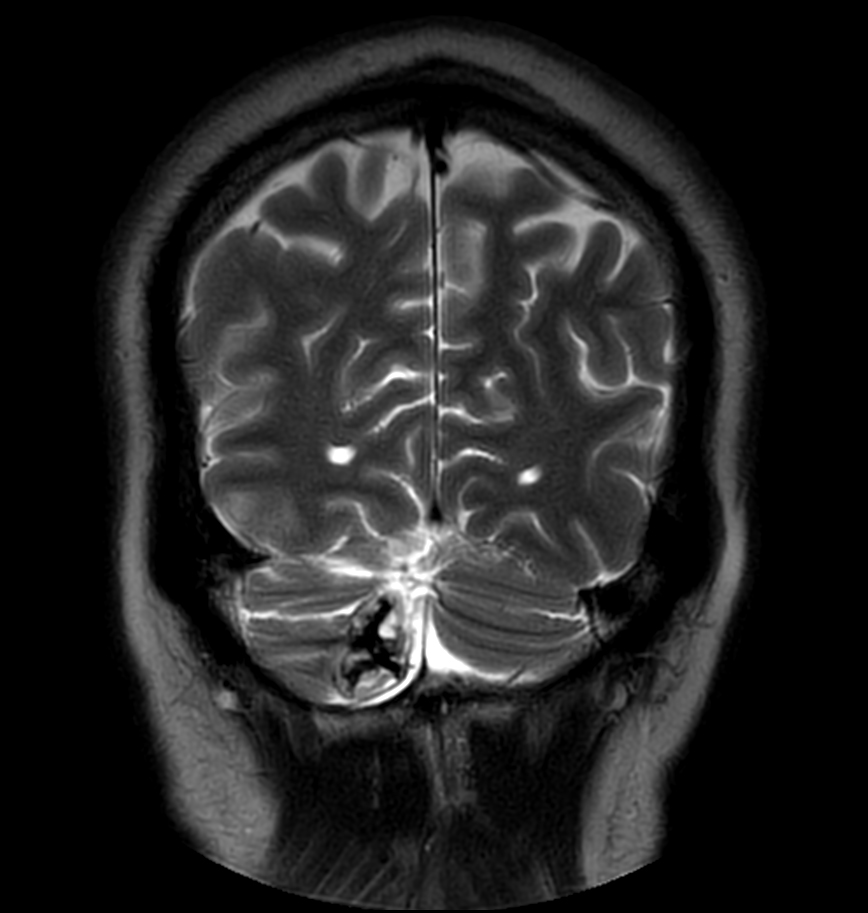

Patient with a lesion in the cerebellum. The ExamCard includes Compressed SENSE to accelerate the entire exam and techniques for motion reduced imaging (MultiVane XD), 3D imaging to acquire high resolution data in multiple directions, 3D susceptibility weighted imaging (SWIp), angiography sequences (Time-of-Flight and Contrast-Enhanced MRA with both arterial and venous phases), DTI with MultiBand SENSE to acquire a high number of diffusion directions in a short scan time and EPIC Brain to bring down any residual distortion.

T2w TSE MultiVane XD